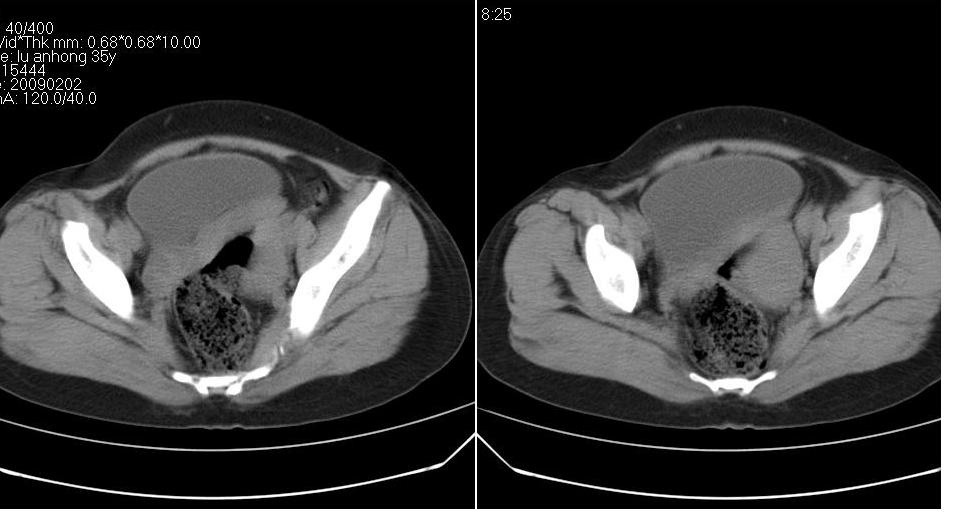

女 35岁,下腹部坠感疼,其它病史不详。图象顺序有点乱。

定位于盆腔附件,有囊性密度,有脂肪密度、还有骨密度;应该是比较典型的卵巢畸胎瘤。